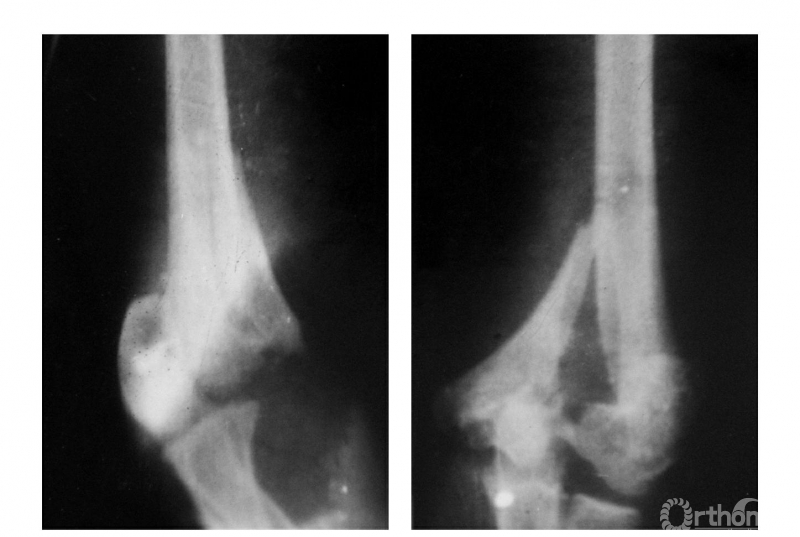

例4:肱骨髁间劈裂性骨折后,内髁骨块向内前移位,外髁骨块向内后移位但两骨块旋转不明显(Ⅱ型)(图4)。

图4